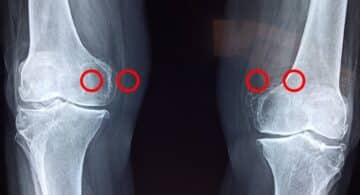

Riabilitazione Cosa sono gli osteofiti e come si presentano Scritto da Silvia AdminSportivaMens - 12 Settembre 2024